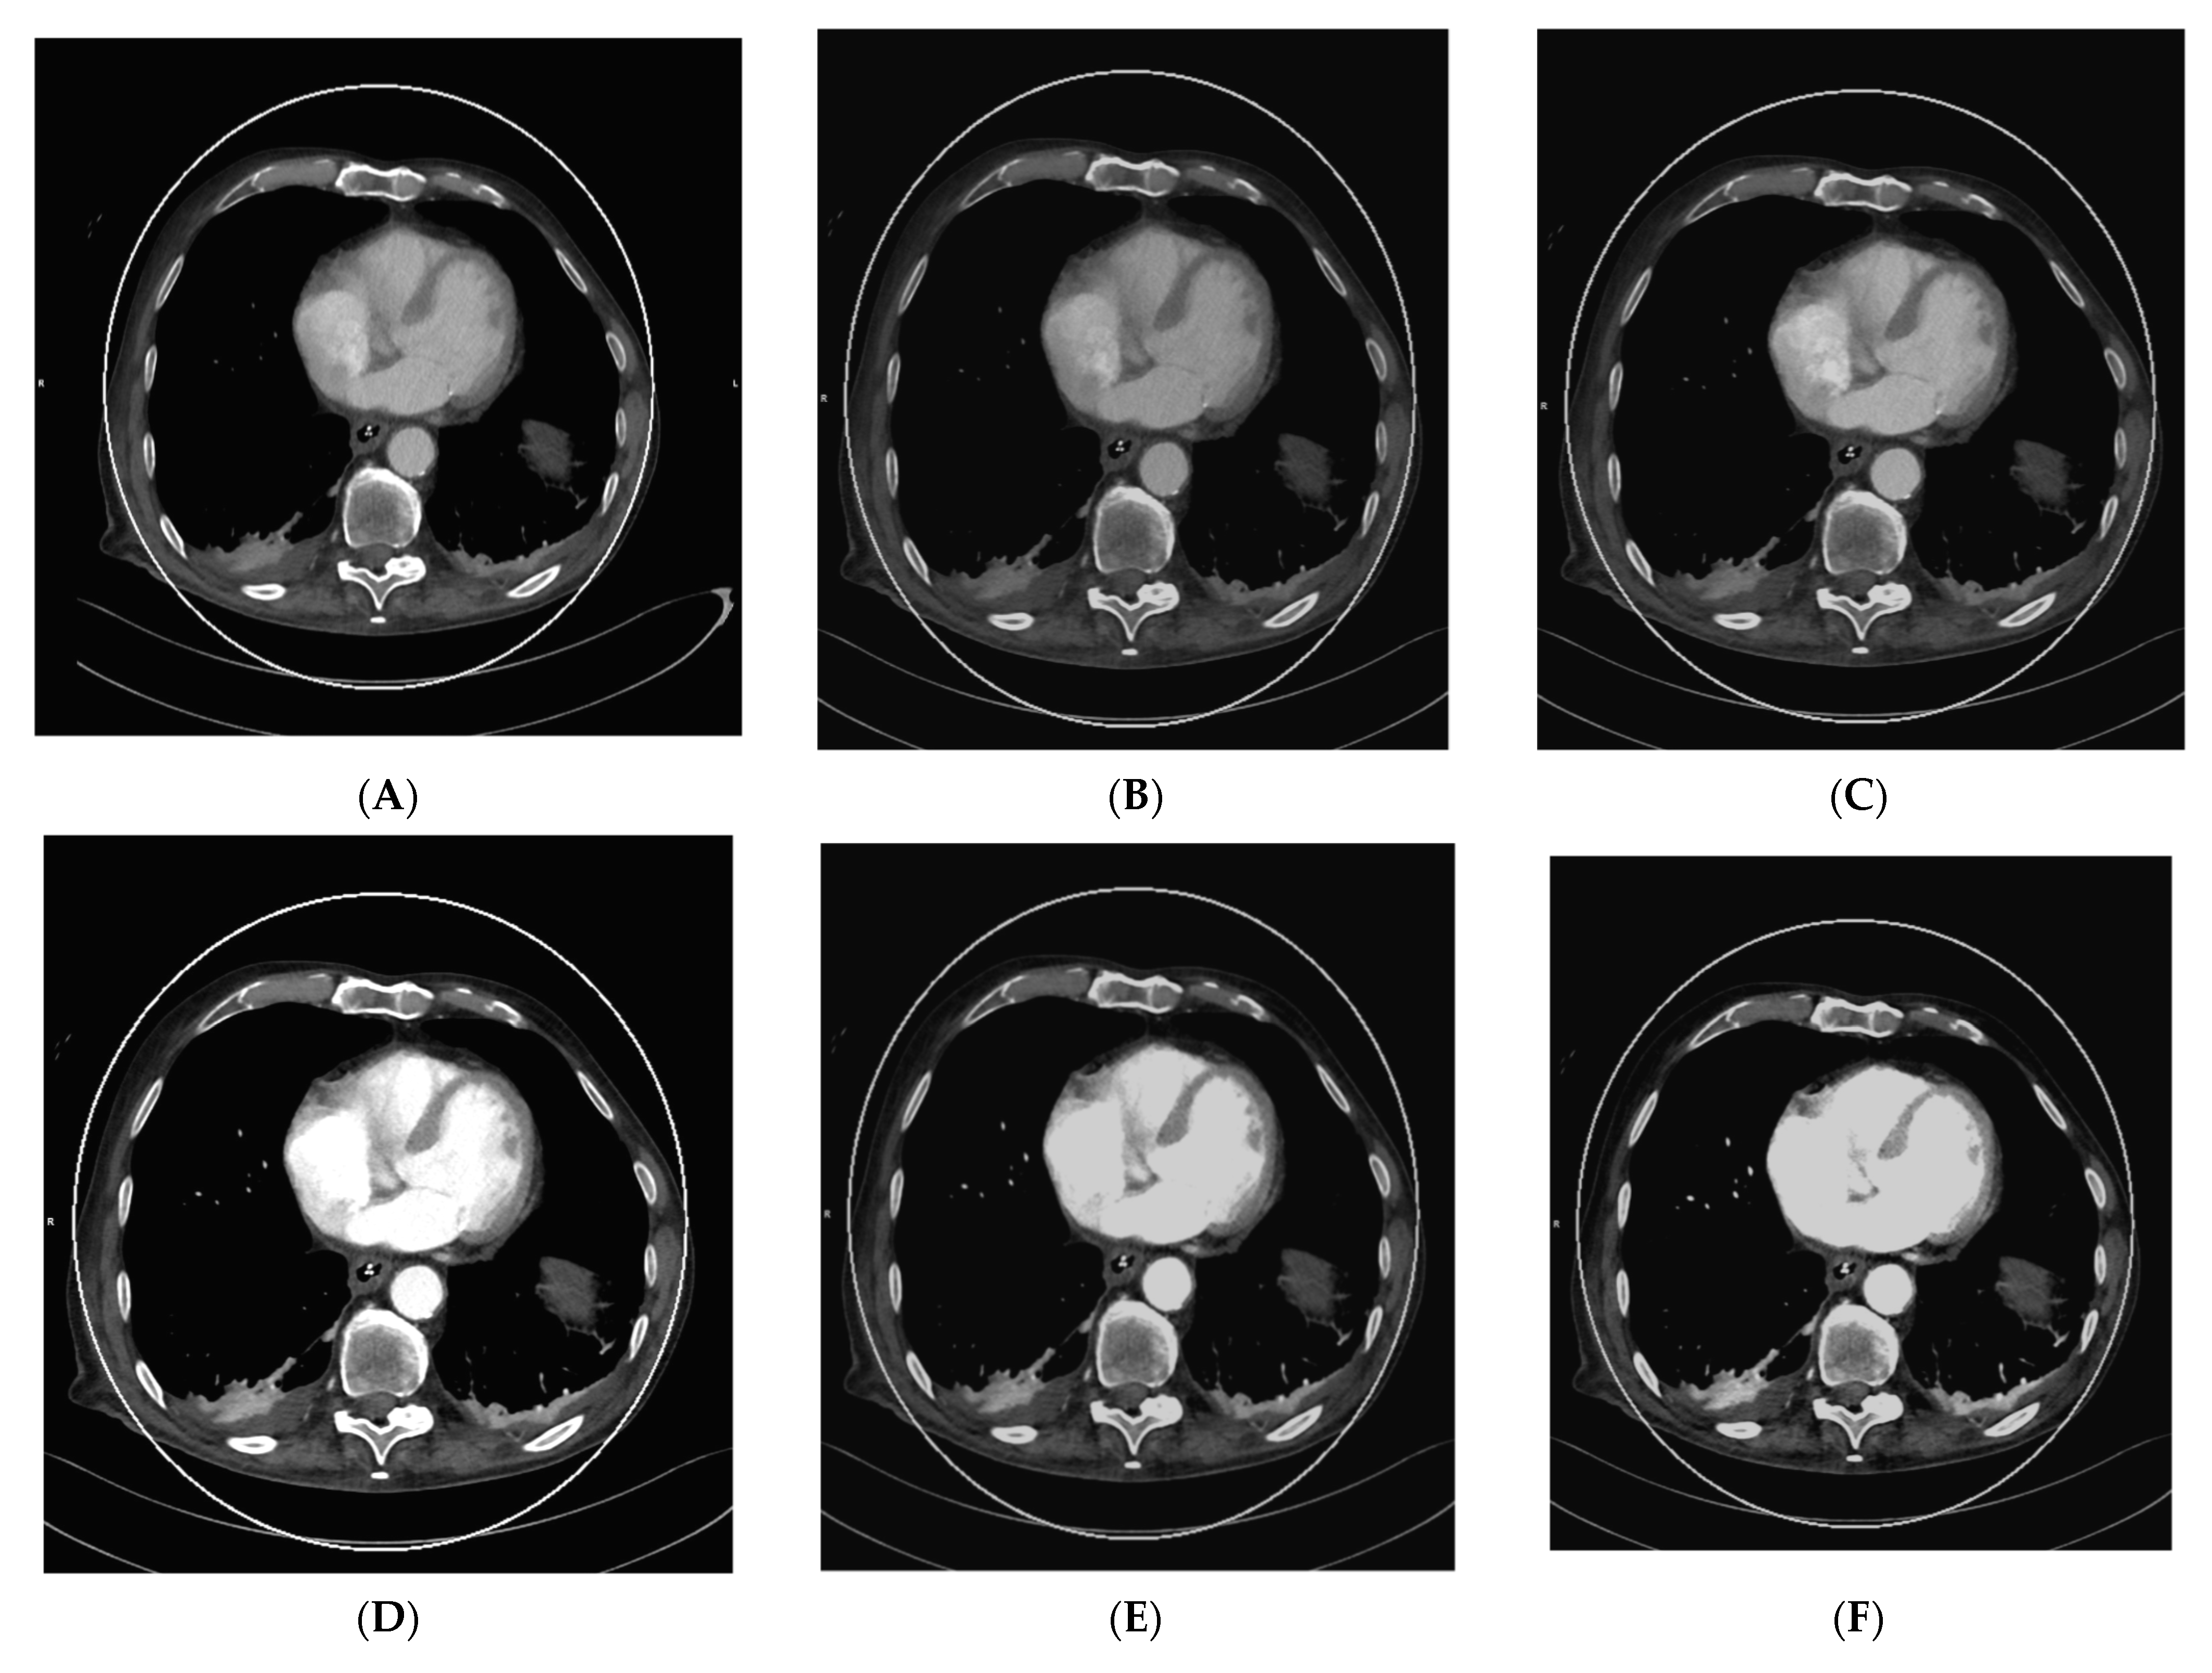

Applications such as color-coded VNCa enable improved visualization of disc herniation (see Figure 4A–D). In 2021, Koch et al. evaluated the diagnostic sensitivity, specificity, and accuracy of color-coded VNCa for the detection of thoracic disc herniation. They found that DECT was significantly better in the tested categories than conventional CT, with a sensitivity of 95% in DECT vs. 73% in SECT and a specificity of 96% in DECT vs. 82% in SECT [64].

Figure 4.

DECT scan of the thoracal spine in a 61-year-old female patient that presented herself with focal pain at the upper back in the clinical examination after slipping and falling on her back. The clinicians suspected a possible vertebral fracture. Thus, a CT scan without a contrast agent was scheduled. During the reading of the images, fractures were ruled out quickly. In the VMI 120 kV soft tissue kernel CT reconstruction, as shown in (A) axial and (B) in sagittal orientation, disk herniation was hardly visible. Application of color-coded VNCa DECT reconstructions finally revealed dorsal median disc herniations (indicated by the white arrows in (D,F)) in segments T 6/7 and T 7/8, as seen in (C) in axial orientation and (D) in sagittal orientation. The finding was later verified in a 1.5 Tesla MRI examination, where the disc herniation could be correlated to the CT findings, as seen in the axial T2-WI sequence (E) and the sagittal T2-WI sequence (F).